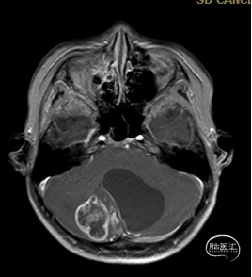

术后MRI

枕下后正中开颅小脑肿瘤切除术

术后病理